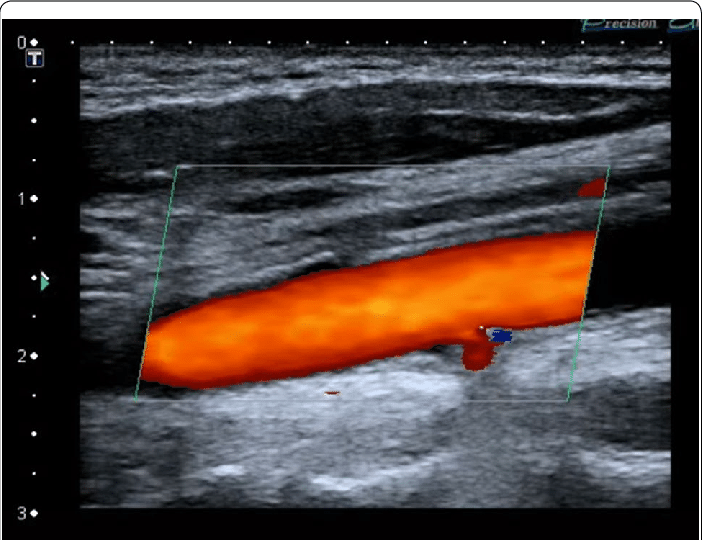

Когда к этому «двойному» режиму добавляется третий компонент - цветовое картирование кровотока (ЦДК), метод называют триплексным сканированием. На экране монитора потоки крови окрашиваются в разные цвета (традиционно красный - к датчику, синий - от датчика). Это не просто для красоты. Цветовое кодирование делает картину еще более наглядной и помогает врачу мгновенно выявлять проблемные зоны: участки турбулентного, завихренного кровотока за атеросклеротической бляшкой или «цветовые утечки» при несостоятельности клапанов.